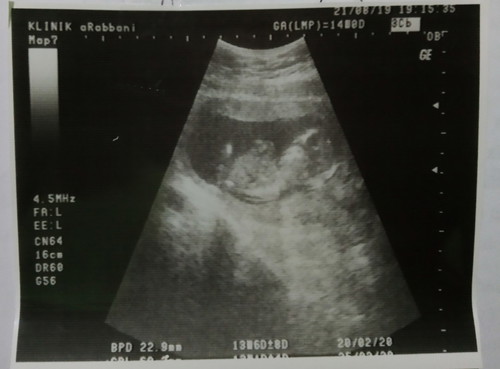

14 week

Assalamualaikum bunda bunda hebat diluar sana, ini hasil USG aku 14 minggu, Alhamdulillah sudah ada kedua tangan dan kedua kaki,sehat, dan aku hamil tanpa gangguan mual apapun, justru makan jadi nafsu sekali, semoga bunda yg lg hamil diberi kesehatan juga ya bayi dan ibunya, dan yg belum semoga cepat hamil ? doakan semoga bayi saya sehat selalu sampai waktu lahirnya, dan lahir dengan selamat sempurna tanpa kekurangan apapun